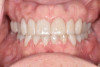

After the restorations were milled, they were sintered and polished for final effect. It was decided that these restorations should not be glazed to avoid the added abrasivity that accompanies this finish to the restoration.22 The patient was then scheduled for temporary crown removal. The final crowns were fitted on the prepared teeth, and the contacts adjusted. The patient reported that she was pleased with the feel and esthetics of the restorations, and the restorations were cemented (Figure 14 through Figure 19).

Fig. 14